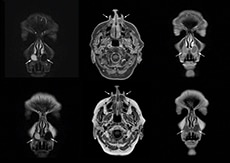

“Imaging cholesteatoma, benign tumors of the middle ear, has been a huge challenge,” says Dr. Heggelman. “We used to do CT, but then we were unsure if we were looking at an inflammation or a cholesteatoma. Also determining if residual cholesteatoma exist after surgery or visualizing recurrence used to be very difficult. Adding Diffusion TSE in our MRI protocol now effectively addresses this.” “Diffusion TSE is far less sensitive to susceptibility differences than previously used EPI sequences. We appreciate the high resolution and the robustness of the sequence. The quality is so good that our confidence has increased. Also our ENT (ear, nose, throat) physicians are excited about the high resolution, the excellent lesion delineation and the sensitivity and specificity.”